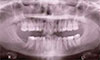

How Do I Handle the Vertical in This Case?

Patient is a 37-year-old female, Class II Div II, a lot of crowding. Is there any good way to handle the vertical problem in this case?